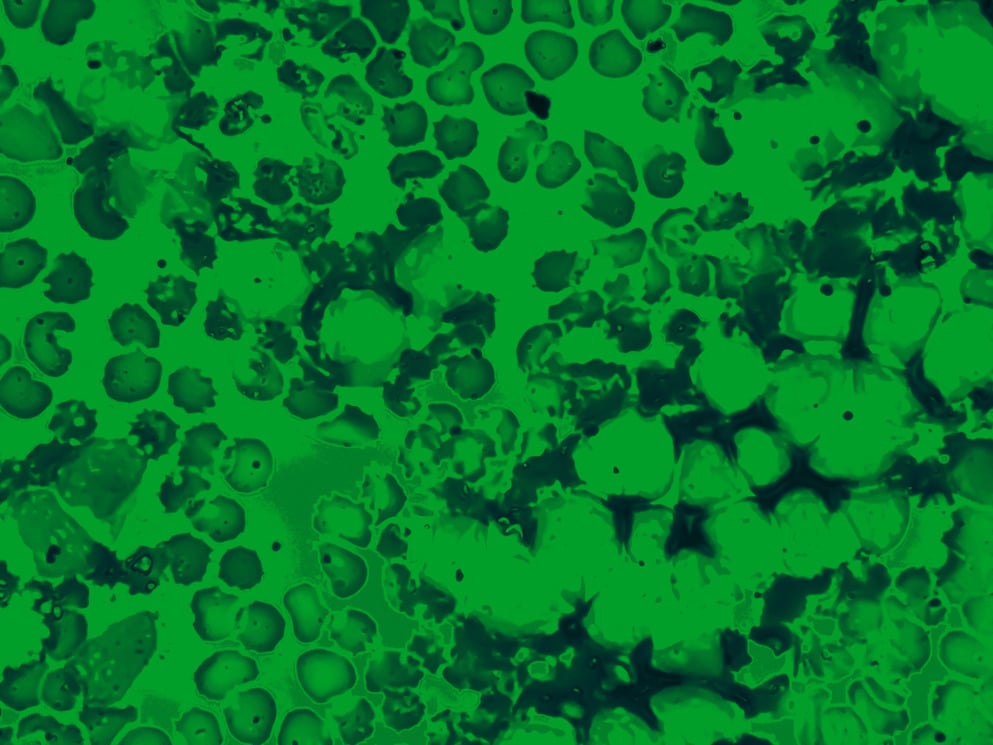

Bone marrow aspirate cytology of multiple myeloma, a type of bone marrow cancer of malignant plasma cells.